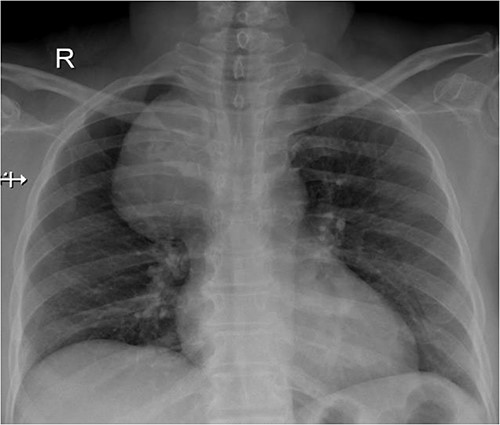

A 57-year-old female came with chest discomfort and cough since 1 month. The chest X-ray (Fig. 1) showed mass in the superior mediastinum. CECT thorax (Fig. 2) revealed the soft tissue density 7 cm × 7 cm (Fig. 3) in superior mediastinum abutting subclavian artery, azygous vein, anteriorly displacing superior venacava, anteromedially abutting arch of aorta, posteromedially compressing trachea and abutting right main bronchus. A 4.9 cm × 5 cm mass in the left side superior mediatinum was seen abutting internal jugular vein and brachiocephalic artery. USG showed the presence of normal thyroid in the neck. CT guided biopsy from the right mass showed ectopic thyroid tissue (ETT)-colloid goiter. Due to close proximity with major vessels sternotomy done. Mass in the left side 5 cm × 5 cm (Fig. 4) in the superior mediastinum was identified, on dissecting superiorly, which was free from the thyroid in the neck and abutting the IJV, brachiocephalic artery and left innominate vein that were separated with meticulous dissection.